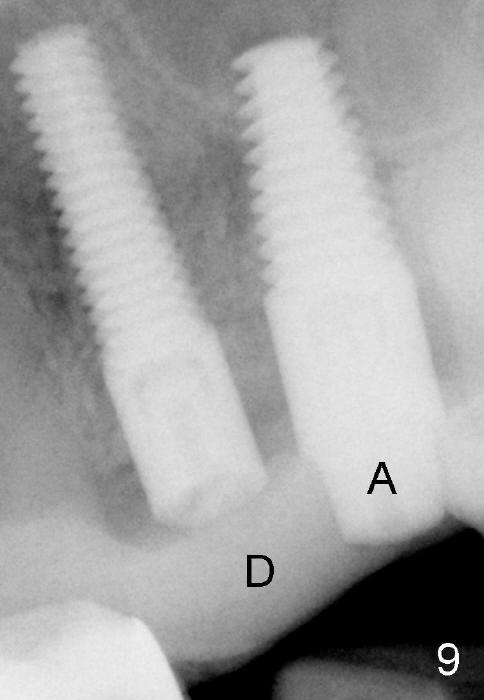

The anterior retainer is kept as a crown at #11 (Fig.2: C), whereas the residual root at the site of #13 is extracted with apical perforation (Fig.3 ^). It is confirmed by Fig.4 (<). To close the perforation, an osteotomy is initiated on the palatal wall of the socket with a 2 mm osteotome (Fig.5 insert: circle). As the osteotomy is being enlarged by a 3 mm osteotome, the bone between the original socket and the osteotomy is being pushed buccally. The former is being closed (Fig.5). The osteotomy is finished with combination of osteotomes and reamers. Fig.6 shows that a 5x14 mm tap is inserted at the site of #13 and that the sinus floor is lifted. In fact the sinus membrane is partially torn at the osteotomy, which is repaired by insertion of Colla-form Dressing (Impladent), followed by autogenous bone (harvested from reamers) mixed with Osteogen (Impladent). A 5x14 mm implant is placed at the site of #13 with insertion torque more than 60 Ncm (Fig.7: I). An incision is made at the site of #12 to start osteotomy with insertion of a parallel pin (Fig.7 P). A 3 mm reamer is kept in place for position confirmation (Fig.8 R). Due to ridge atrophy (Fig.2 arrowheads), a much smaller, but longer implant is placed at the site of #12 (Fig.9: 4x17 mm). The autogenous bone harvested from #12 osteotomy is placed in the buccal gap of #13, followed by insertion of Colla-form Dressing (Fig.10 M). To protect the membrane, a short abutment (4x3 mm) is temporarily placed (Fig.9,10 A) and perio dressing (Fig.9 D) is applied around the abutment and the interproximal areas of the neighboring teeth. Usually perio dressing dislodges around 1 week postop, particularly for a large edentulous space. In this case, the dressing is quite stable 11 days postop: the abutment (Fig.11 A) appears to contribute to retention of the dressing (D).

Three month follow-up shows that the gingiva and bone heal around these two implants (Fig.13-15). Crowns are cemented 4.5 months postop (Fig.16). There is no or minimal bone loss 9 months post cementation (Fig.17, as compared to Fig.15). The bone is stable around the implants 18 months post cementation (Fig.18 panoramus). Root canal therapy is done at #14 between the last follow up appointments.